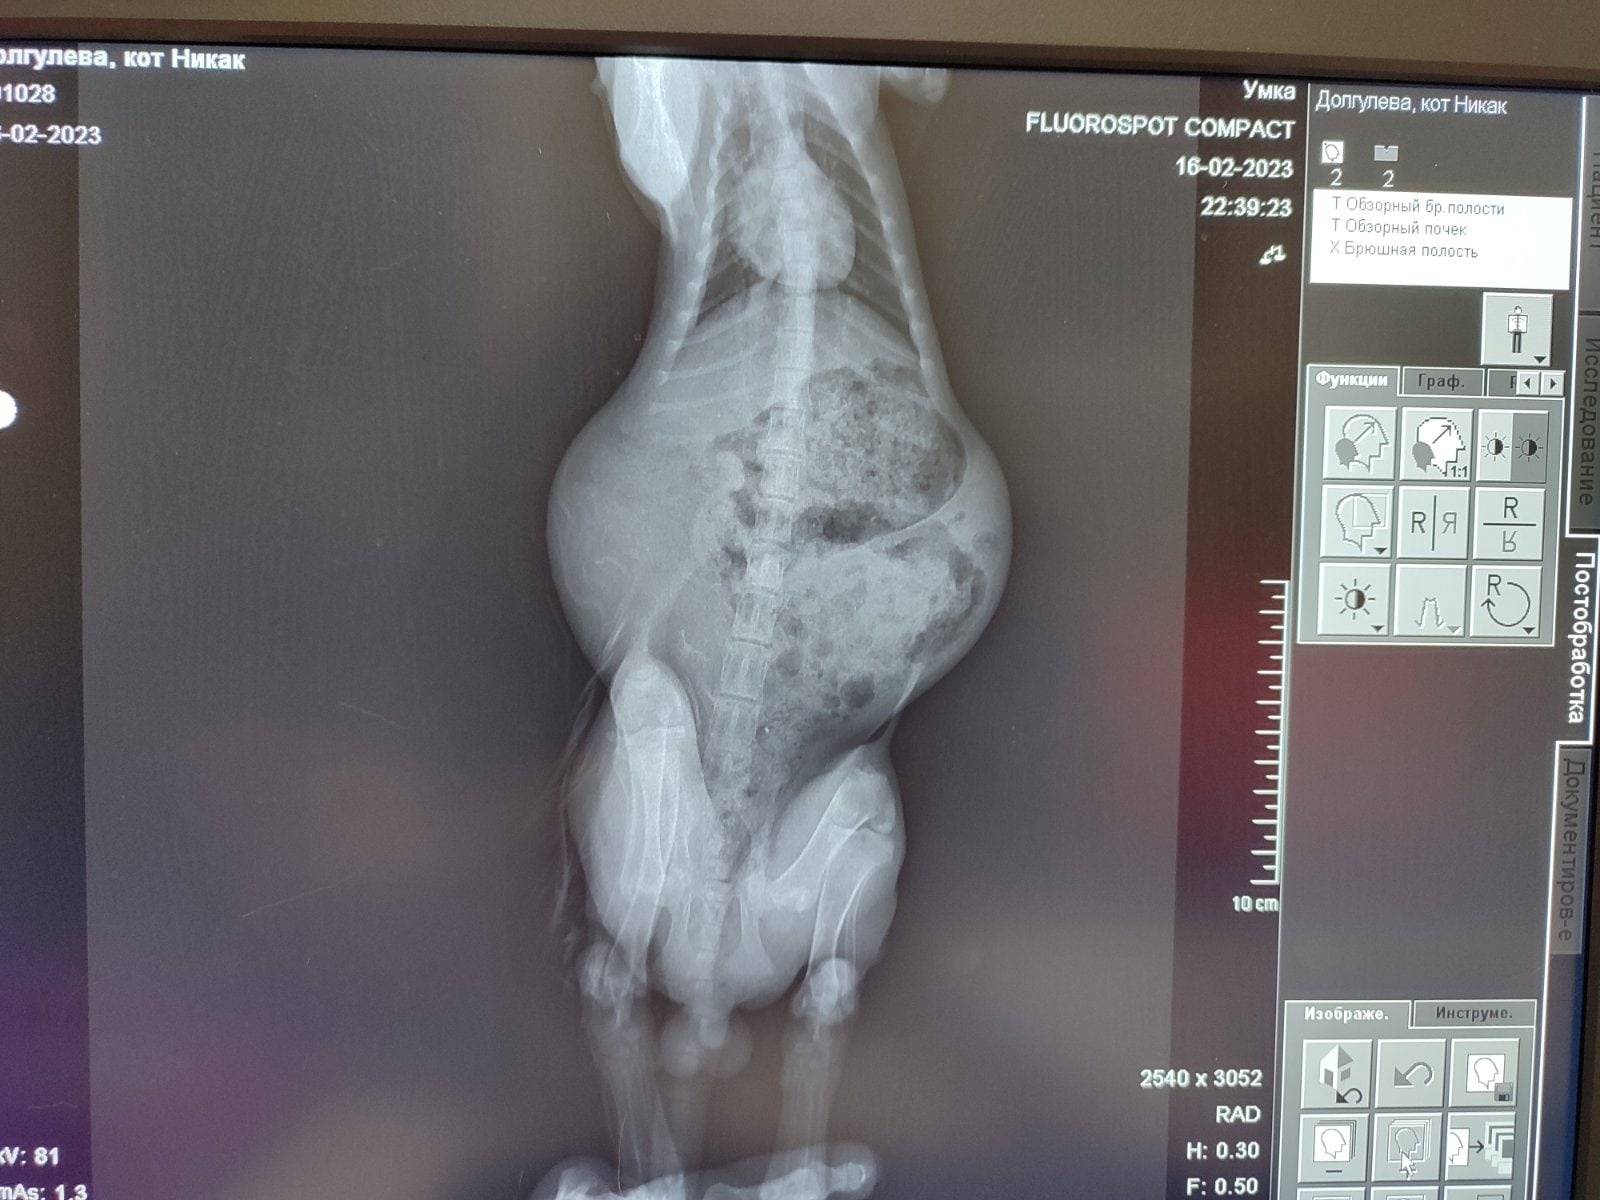

Владелец приюта Марина, свозила котенка на приём к другому, проверенному нами врачу УЗИ. По результатам УЗИ и рентгена прояснилось, что асцита у котенка нет, зато кишечник и желудок полностью забит каловыми массами, а мочевой переполнен. Позвоночник "волнами", кости "прозрачные". Котенка катетеризировали и отвели мочу, чтобы ему стало полегче. Ну а дальше это уже пациент ортопеда, т.к. ни терапевт, ни врач УЗИ не были здесь компетентны.

Приём у ортопеда прояснил всю ситуацию. У котенка алиментарный (вторичный) гиперпаратиреоз или как ее еще называют - болезнь хрупких косточек.

Кормление только одним мясом или "натуральное" кормление", чаще всего с человеческого стола (мясо, каши, молочные продукты) не дают организму животного необходимое количество минеральных веществ. Фосфора в организм поступает во много раз больше, чем кальция и витаминов. Низкий уровень кальция в рационе приводит к снижению уровня кальция в крови животного, а это, в свою очередь, приводит к повышенной выработке паратгормона паращитовидной железой. Под действием этого гормона начинается усиленное выведение кальция из естественного депо (т.е. костей скелета) и передача его в кровяное русло для поддержания нормального состава крови. При этом скорость разрушения костей оказывается выше скорости образования новой костной ткани. Кости истончаются, становятся слабыми и хрупкими. Избыток фосфора еще сильнее усугубляет проблему тем, что мешает нормальному усвоению кальция в кишечнике.

Т.е. котенок испытывает боли, из-за чего не может принять естественную позу, чтобы помочиться и опорожниться. Он просто терпит до последнего, отчего все копится в мочевом и кишечнике. Отсюда и задержка мочи и очень сильное вздутие кишок. По этой же причине и искривлен позвоночник.